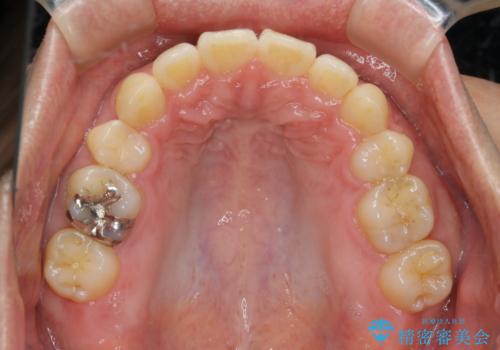

がたつき、口ゴボ(出っ歯)、真ん中のずれを抜歯矯正治療で治す。ワイヤー矯正治療

- 矯正装置

- ワイヤー矯正 審美装置

- 治療計画

- 口元の突出感とがたつきを気にして来院されました。

突出感とがたつきの改善を行うために大きなスペースが必要であったため、親知らず以外の歯を4本歯を抜歯する計画を立てました。

もともとの歯の根っこの位置の関係で、治療途中において上下の真ん中の位置がずれてしまいました。機能的には問題ありませんが患者様と相談し、期間を延ばした上で真ん中を合わせる治療を追加で行いました。